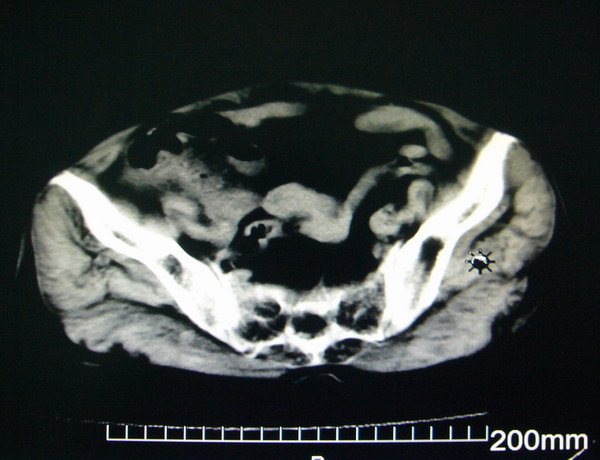

女:83y,转移性右下腹痛2小时,白细胞计数增高。

1.右侧肾盂扩大,肾盏无扩张,考虑:先天性肾盂变异可能性大。

2.胆囊扩张,考虑:胆囊炎。

3.阑尾区域可见以结节样高密度影,结合病史,考虑:阑尾结石,阑尾炎。

右下腹肠系膜增厚,结合病史支持阑尾炎.

右侧壶腹型肾盂可能,建议输路造影或增强

1.右侧肾盂扩大,考虑先天性肾盂变异或肾盂旁囊肿。

2.胆囊扩张,考虑胆囊炎。

3.阑尾区域可见结节样高密度影,结合病史考虑:阑尾结石、阑尾炎。